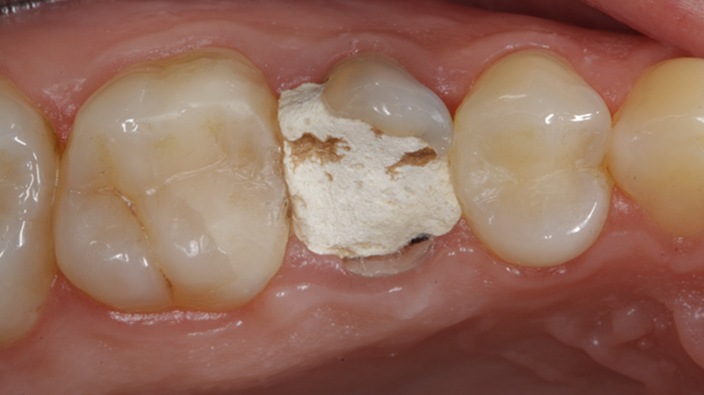

Clinical case: Extraction, immediate implant placement, & provisionalization

- Courtesy of Dr. Iulian Filipov, Romania -

AnyRidge, R2GATE, guided surgery, immediate placement, immediate provisionalization, initial stability, Dr. Iulian Filipov, #25, maxillary posterior, immediate loading, Mega ISQ

Products: